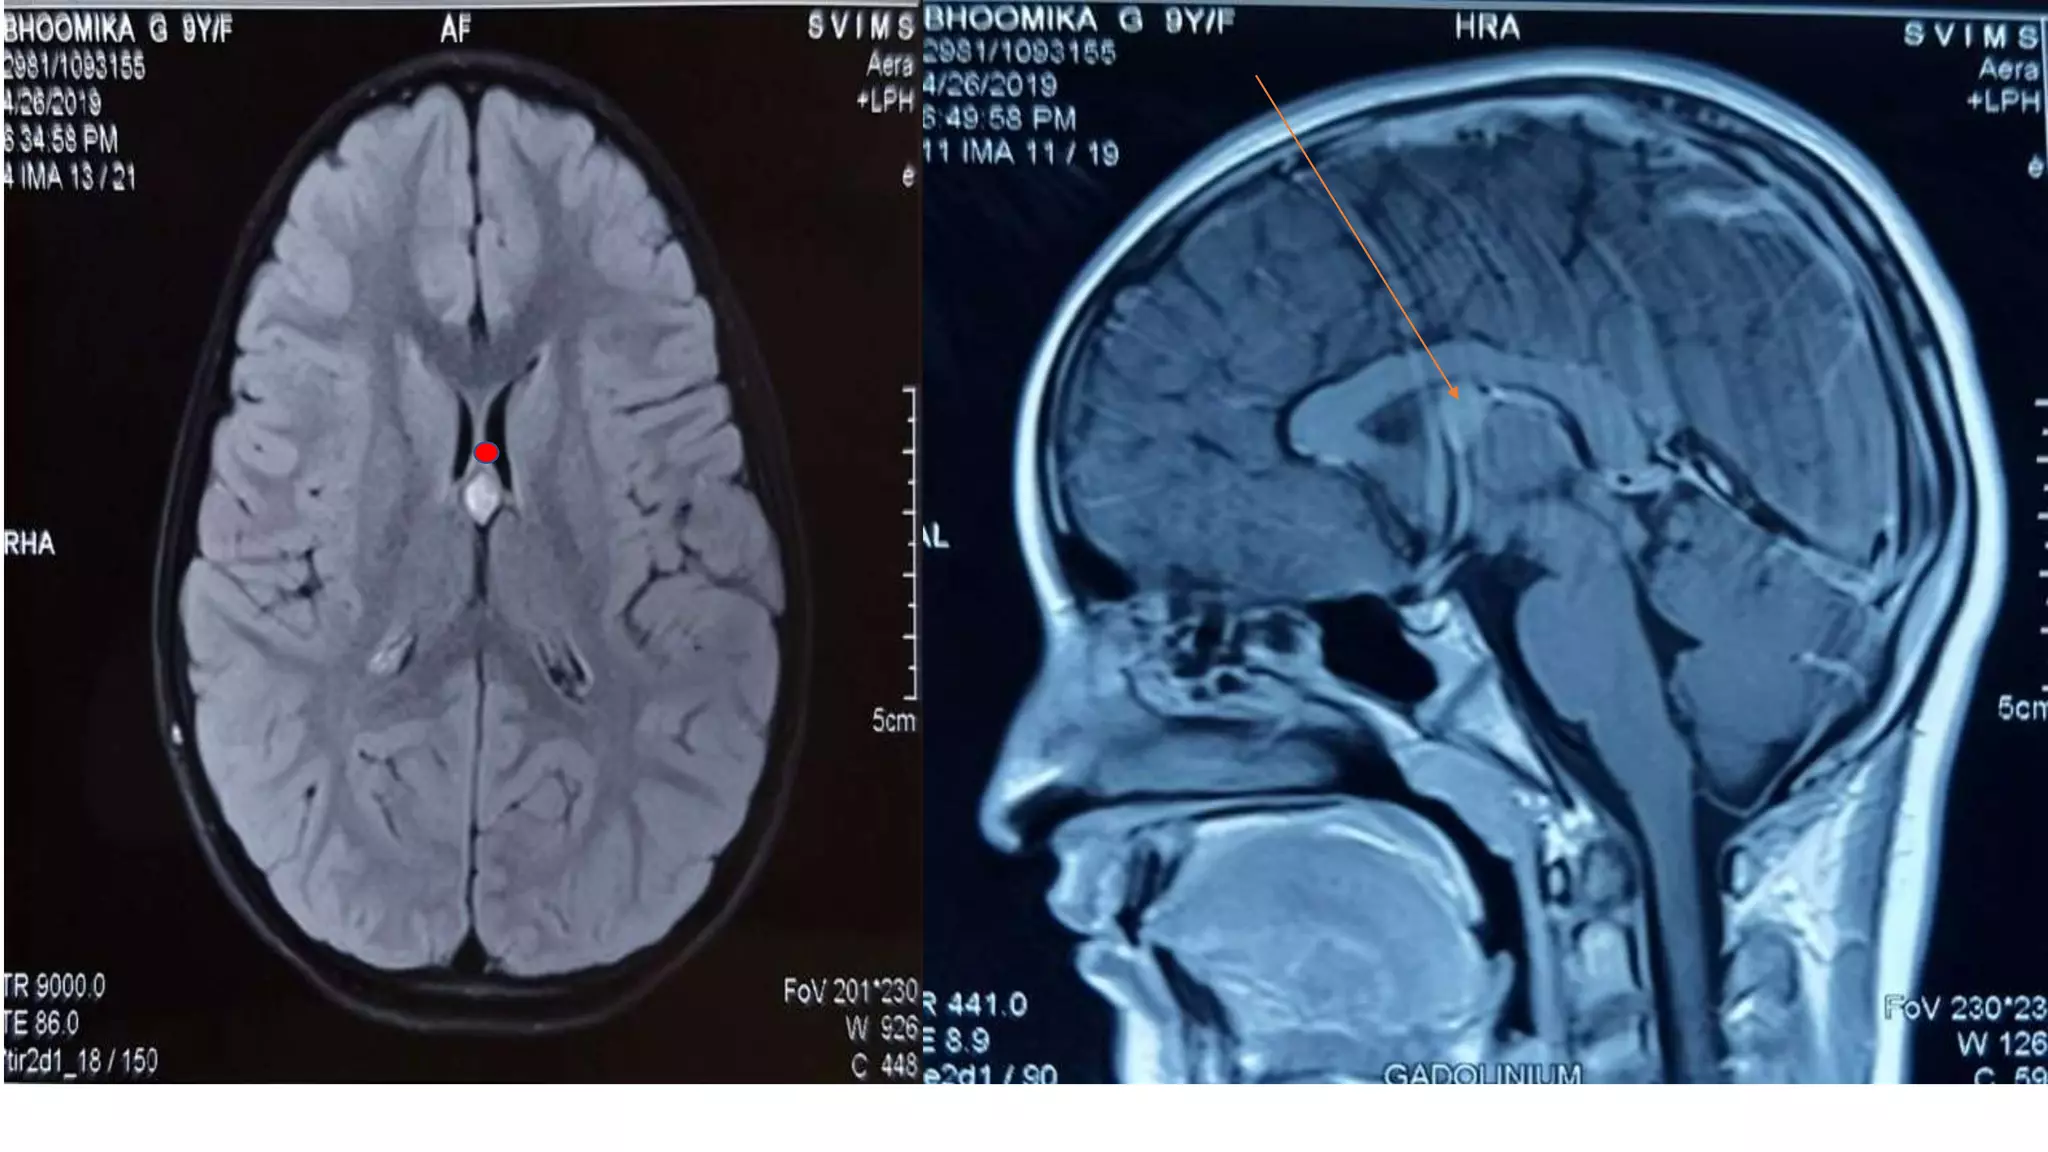

Colloid cyst

• Most common age 20-40

• Roof of third ventricle

• Drop attack and signs of raised ICP

• Neurogenic stunned myocardium cause of sudden death